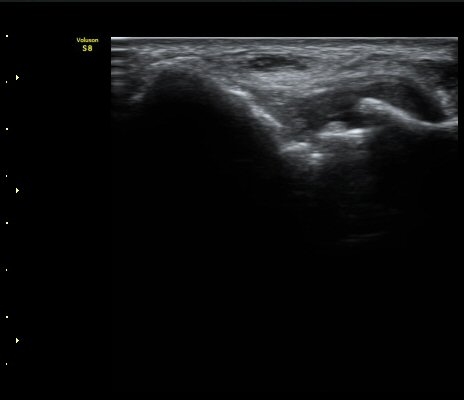

[ÆÈ²ÞÄ¡] ÆÈ²ÞÄ¡ °üÀý³» À¯¸®Ã¼¿¡ ÀÇÇÑ ÆÈ²ÞÄ¡ ÅðÇ༺ °üÀý¿°

¼ºº° / ³ªÀÌ

³²ÀÚ/ 44¼¼

ÁÖÁõ»ó

ÆÈ±ÀÄ¡ ÅëÁõ

ÃÊÀ½ÆÄ °Ë»ç